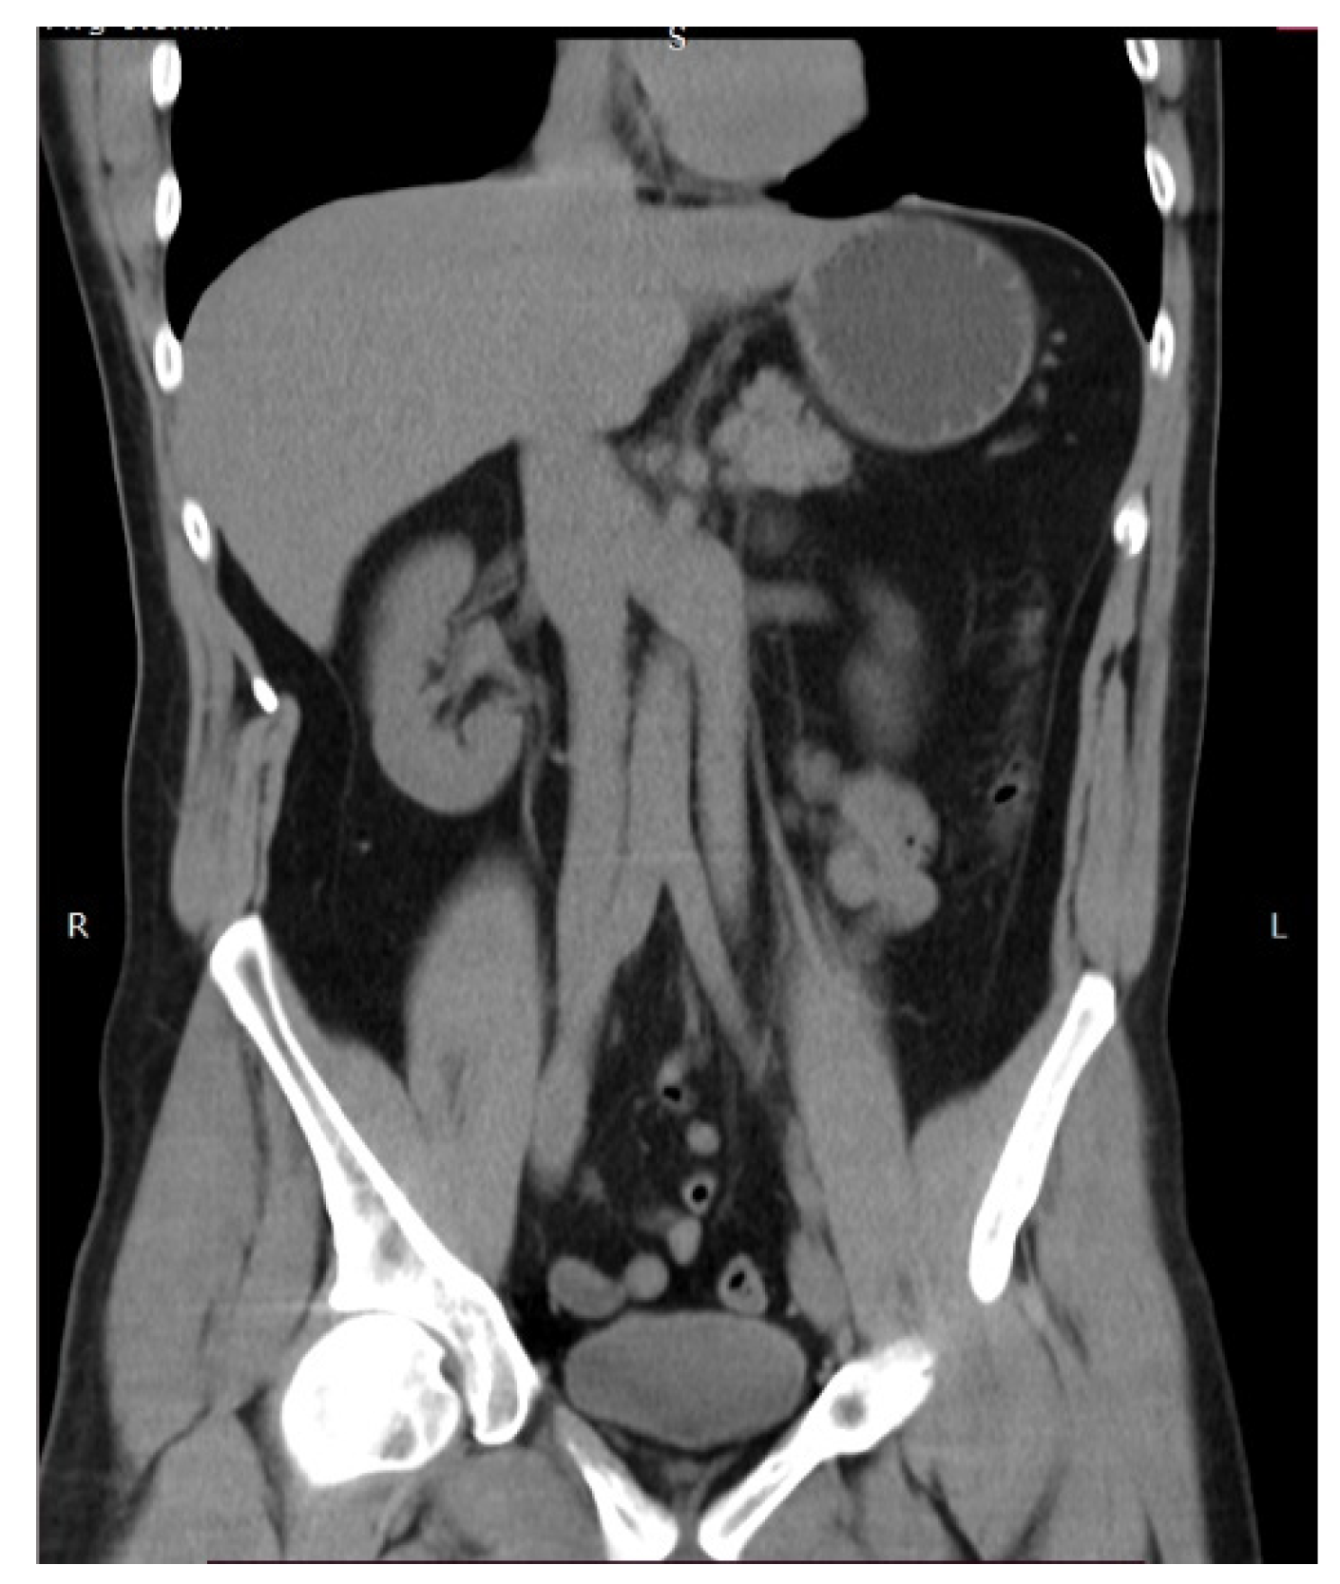

9.4.2. Duplication of the Inferior Vena Cava

Surgical Considerations